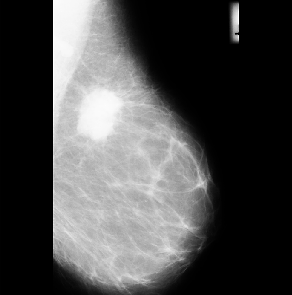

Filtering is a technique for removing unwanted information from an image by perception and making it more suitable for the next step in image processing. To remove speckle sounds from photos, various types of filtration are used. The image was de-specked using a mean-median filter in this investigation. The image before and after applying the mean-median filter is shown in Figure 2(b) and 2(b), respectively.

Figure 2. (a) Input image (b) denoised image after mean- median filter